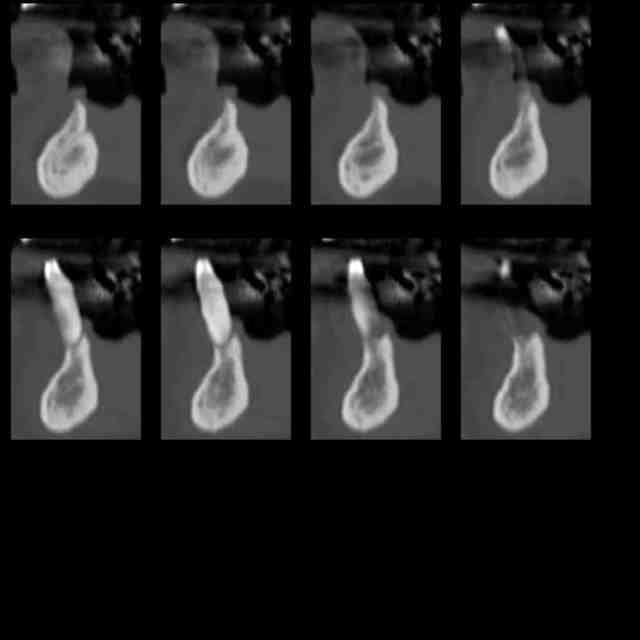

Voilà la pano et les coupes de scan de la dent 44 à 35.

Scan 1 calhxm - Eugenol

Scan 2 lozwjp - Eugenol

Scan 3 qvvm5h - Eugenol